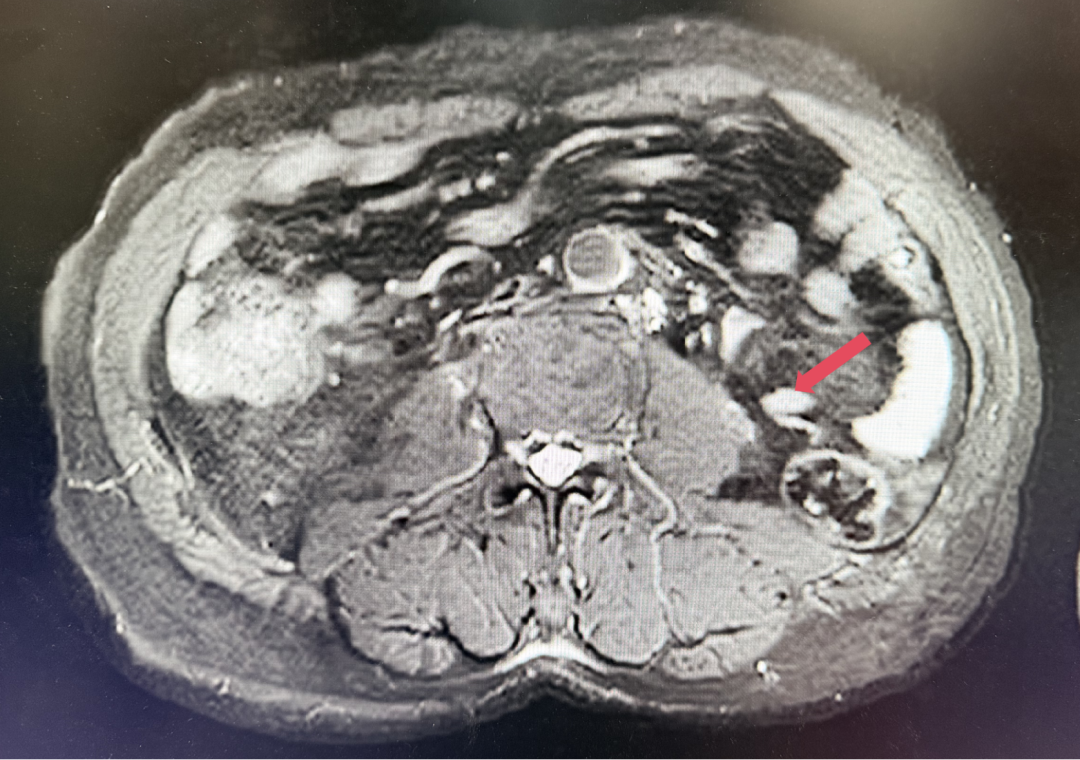

2023年3月,初始应答

2023年3月:用药6周(C2)后首次肿评,肿瘤负荷减少至76.8mm,达到PR。